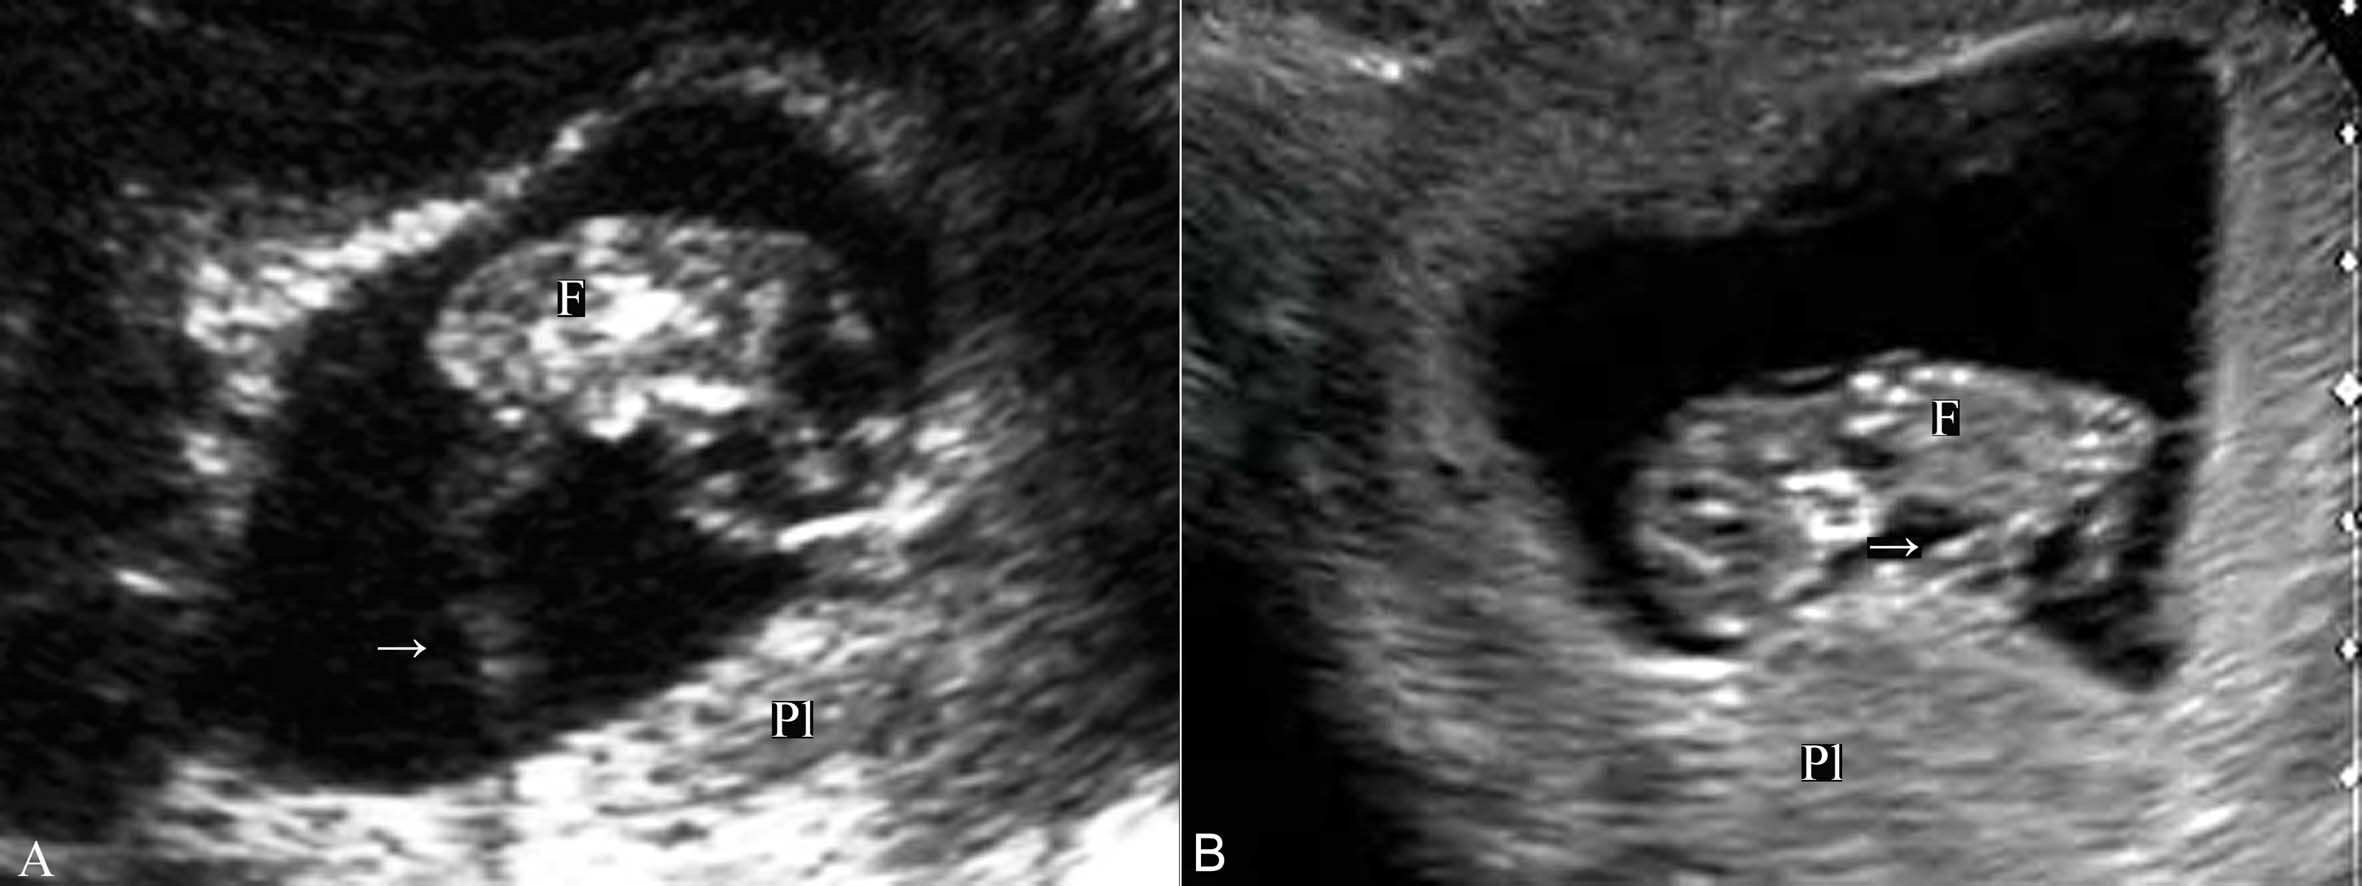

早期妊娠时超声显像检查显示胎盘回声后即可显示脐带血流。宫腔内超声显像检查在停经后第 7 周可以显示胚胎与胎盘之间联接的脐带,彩色多普勒血流显像检查可以清晰地显示脐带血管的血流;经阴道和经腹超声显像检查可在第8~9孕周显示脐带回声,呈索状强回声,直接联接在胚胎和胎盘之间(图2、3),由于此期内脐带多较短,致使胚胎与胎盘的位置相对固定;脉冲多普勒可以清楚地记录到脐动脉收缩期三角形的血流频谱,舒张期可无血流显示(图5A)。

图2早孕期脐带声像图